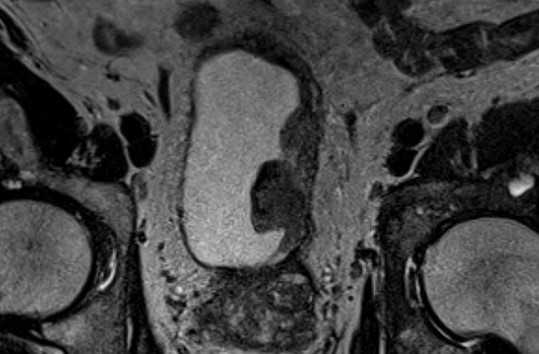

МРТ малого таза в корональной плоскости. Вдоль левой боковой стенки мочевого пузыря отмечается объемное образование, с неровными бугристыми контурами, инфильтрирующее мышечную стенку мочевого пузыря, без распространения за пределы органа. Определяются МР-признаки вторичного поражения (метастазы) левой подвздошной и седалищной костей.